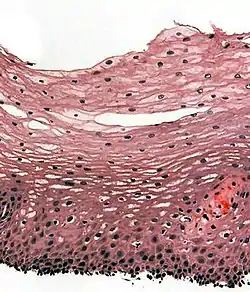

H&E stain of biopsy of normal esophagus showing the stratified squamous cell epithelium.

A stratified squamous epithelium consists of squamous (flattened) epithelial cells arranged in layers upon a basal membrane. Only one layer is in contact with the basement membrane; the other layers adhere to one another to maintain structural integrity. Although this epithelium is referred to as squamous, many cells within the layers may not be flattened; this is due to the convention of naming epithelia according to the cell type at the surface. In the deeper layers, the cells may be columnar or cuboidal.[1] There are no intercellular spaces. This type of epithelium is well suited to areas in the body subject to constant abrasion, as the thickest layers can be sequentially sloughed off and replaced before the basement membrane is exposed. It forms the outermost layer of the skin and the inner lining of the mouth, esophagus and vagina.[2]